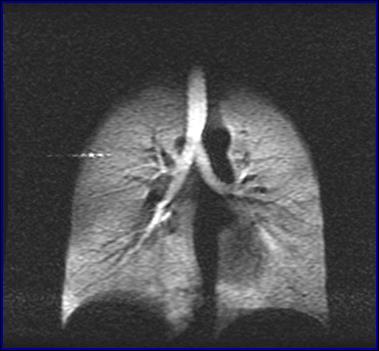

中國科學(xué)院武漢物理與數(shù)學(xué)研究所研究員周欣、中科院院士葉朝輝帶領(lǐng)的科研團(tuán)隊(duì)克服技術(shù)難關(guān),研制出具有自主知識(shí)產(chǎn)權(quán)的人體肺部氣體磁共振成像系統(tǒng)。該系統(tǒng)彌補(bǔ)了傳統(tǒng)磁共振成像不能檢測肺部空腔結(jié)構(gòu)的缺陷,成功“點(diǎn)亮”人體肺部,且能同時(shí)獲得肺部氣氣、氣血交換的功能信息,成為肺癌等重大疾病早期科學(xué)研究和診斷的新利器。目前,該成果已轉(zhuǎn)移轉(zhuǎn)化成立產(chǎn)業(yè)化公司,且正在申請(qǐng)醫(yī)療器械注冊(cè)證。2018年7月在同濟(jì)醫(yī)院建立了第一個(gè)肺部氣體磁共振臨床檢測中心,用于大規(guī)模臨床病例獲取工作。

人體肺部氣體磁共振成像系統(tǒng)

左:核心裝置超極化氣體發(fā)生器 右:我國首幅人體肺部氣體磁共振成像圖